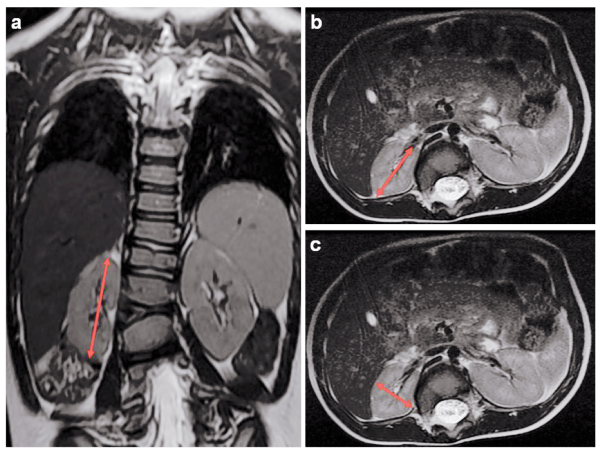

由张锋教授领导的这项研究利用全外显子组测序和CGH芯片方法,从中国和美国的多中心病例样本中鉴定到102例16p11.2/TBX6缺失的携带者,通过回顾临床数据,发现25%的亚裔突变携带者和16% 的高加索裔/西班牙裔突变携带者有先天性肾脏和尿路畸形(图1)。这个患病比例远高于普通人群中1/1000的先天性肾脏和尿路畸形比例。同时,该研究团队回顾了7例TBX6基因点突变携带者的临床数据,发现其中4例是先天性肾脏和尿路畸形患者,存在肾脏发育不全等问题。然后,该团队利用CRISPR基因编辑技术建立了一系列具有不同Tbx6基因表达水平的突变小鼠模型,并对小鼠肾脏表型进行深入分析,明确了小鼠Tbx6基因缺陷会导致肾脏发育的异常(图2)。随着Tbx6基因表达量降低,小鼠肾脏发育异常的风险也随之升高。该研究成果可以为先天性肾脏和尿路畸形的分子诊断、遗传咨询和临床干预提供新的理论指导。